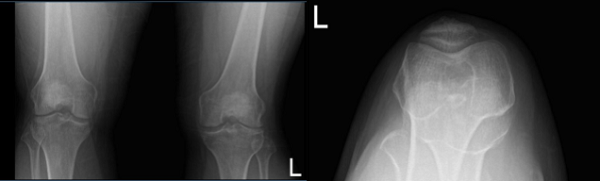

Case Study: Knee Arthroscopy: Repair of the Lateral Meniscus

Chondroplasty of Patella and Lateral Femoral Condyle

in a 30-year-old Man

An MRI and X-ray were performed, which shows lateral meniscus tear. We discussed treatment options and the patient opted for surgical management. We discussed the risks and benefits and complications of the surgery. We discussed possible meniscal repair versus meniscectomy. The patient understood and signed an informed consent.